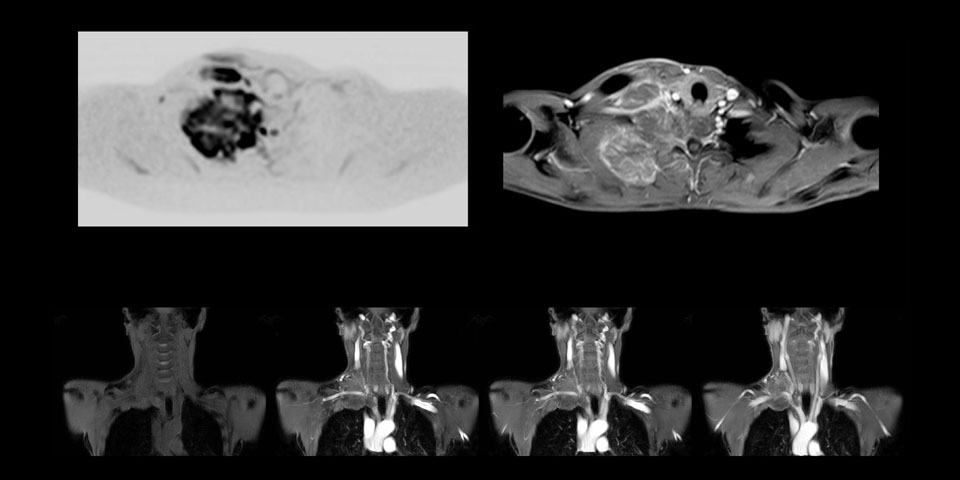

MRI of Pancoast tumor

Although the area between the neck and the top of the lung is one of the most difficult areas for MRI, Prodiva 1.5T images show good quality in this 56-year-old male with Pancoast tumor on the right. mDIXON TFE images shows excellent fat suppression in the neck area and the DWI shows almost no distortion.

MRI of Pancoast tumor

Although the area between the neck and the top of the lung is one of the most difficult areas for MRI, Prodiva 1.5T images show good quality in this 56-year-old male with Pancoast tumor on the right. mDIXON TFE images shows excellent fat suppression in the neck area and the DWI shows almost no distortion.